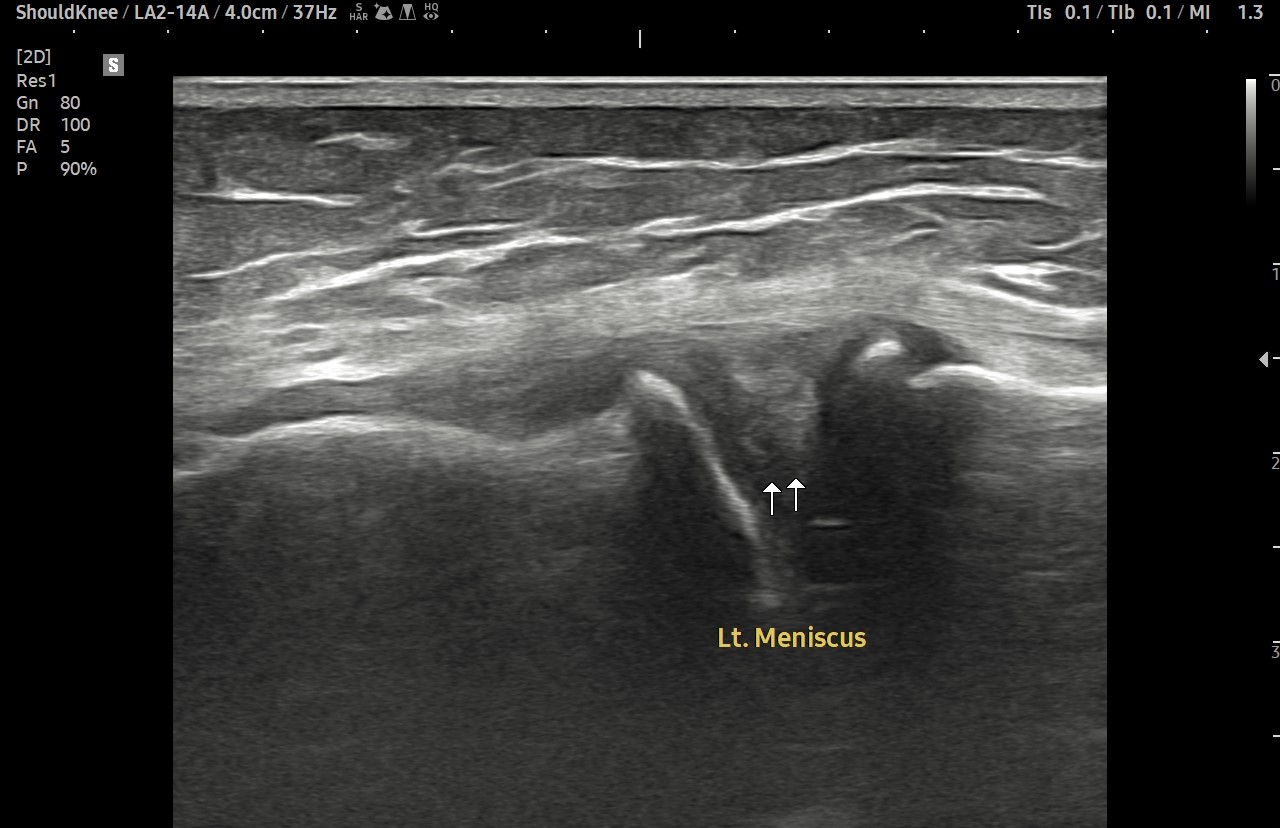

- 치료기간 : 2025 . 6 . 14 ~ 2025 . 7 . 25

- 치료횟수 : 10 회(2cycle)

치료 전

치료 후